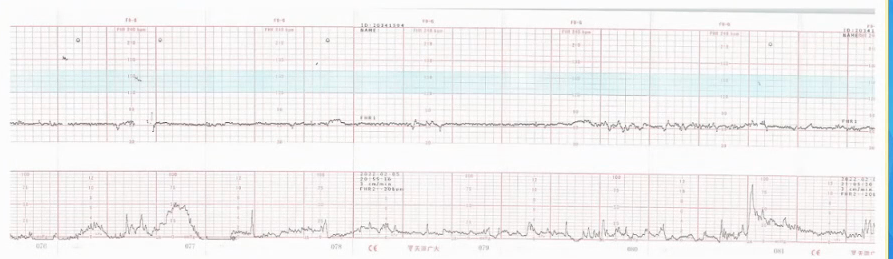

电子胎心监护是产科医护人员必备的一项基本功,只有掌握电子胎心监护的规范应用、识图技巧以及后续快速到位的应急处理,才能保证围产儿的健康安全。本期【每周一课】由四川大学华西第二医院的姚强教授就电子胎心监护的基本知识、判读要点及案例进行了详细的讲解。